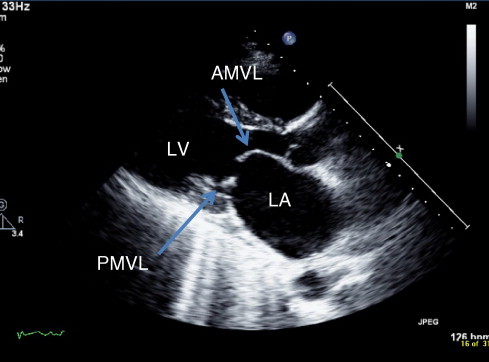

Identify appropriate investigations for mitral stenosis